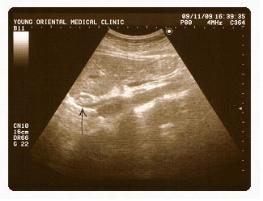

▲ 역류성식도염환자 식도 (위장부위 초음파 단면사진)

<사진출처> : 강남 영한의원 최승영원장